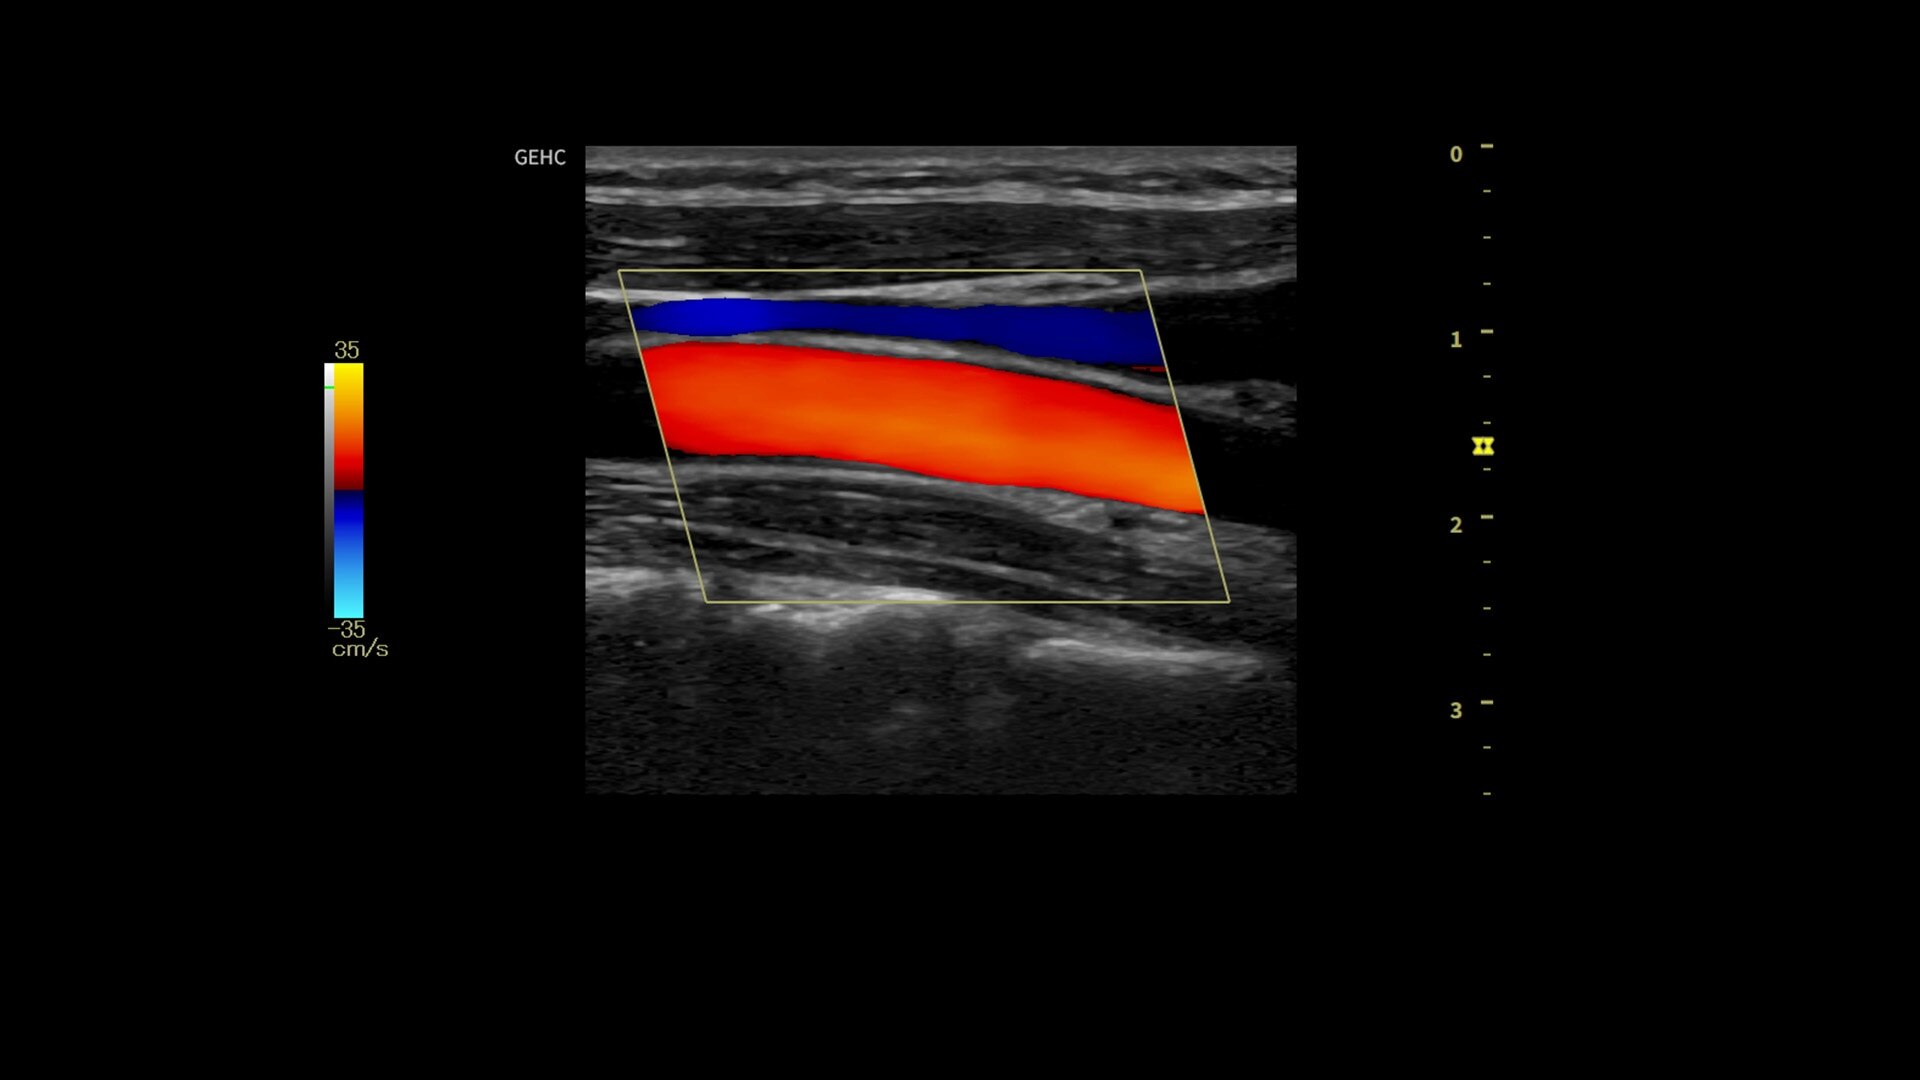

• Optimize images while scanning with Whizz clinical features, easily improve Color Doppler with Whizz Color Flow, and view scans in the image style that suits your preference with Whizz Easy Style